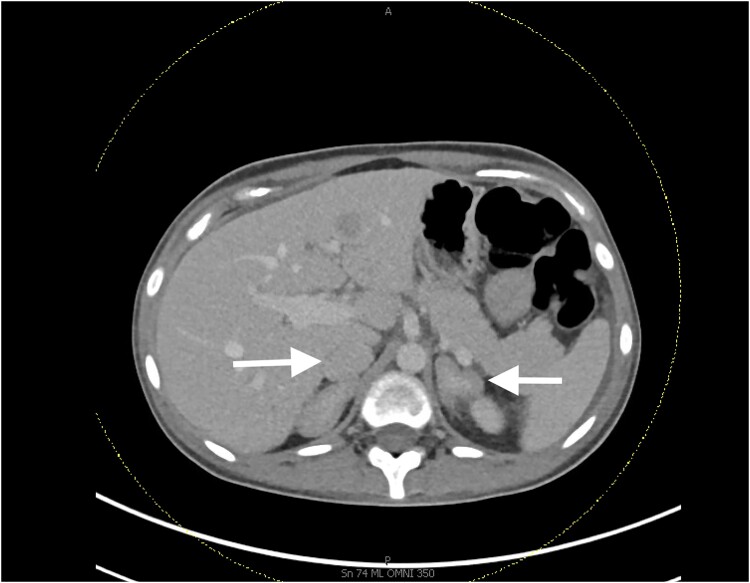

Cushing syndrome due to ectopic adrenocorticotropic hormone (ACTH) secretion (EAS) is rare and may progress rapidly, making treatment very challenging. We report a 27-year-old woman with metastatic neuroendocrine tumor (NET) who presented with sudden onset and rapidly progressing fatigue, muscle weakness, and weight gain. Laboratory findings confirmed severe EAS with new onset hypocalcemia, hypokalemia, and hyperglycemia. The patient was hospitalized and initiated on high-dose osilodrostat. Cortisol levels rapidly decreased in response to osilodrostat. During treatment, she developed glucocorticoid withdrawal symptoms for which hydrocortisone treatment was started. Due to her ineligibility for bilateral adrenalectomy, bilateral adrenal arterial embolization was attempted but ultimately converted to right-only embolization due to hypertensive urgency and difficulty in catheterization. With significant improvement of cortisol levels, her hypocalcemia, hyperglycemia, and hypokalemia resolved. Her osilodrostat dose was gradually lowered during follow-up. Glucocorticoid replacement continued as part of the ongoing block-and-replace regimen.